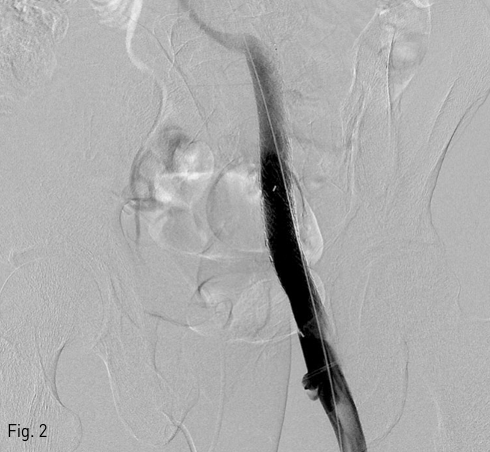

좌측 외장골정맥 aneurysm에 대한 스텐트-그라프트 설치 8개월 뒤 CT 상 aneurysm의 크기가 약 3.5 X 3.3 X 3.0 cm로 감소하였으며 (Fig. 3A), 3년 5개월 뒤 CT에서 aneurysm이 거의 남아 있지 않았다 (Fig. 3B)

Fig 3B

At 8 (A) and 41 (B) months follow-up CT show a gradual decrease in size and complete disappearance of aneurysm.